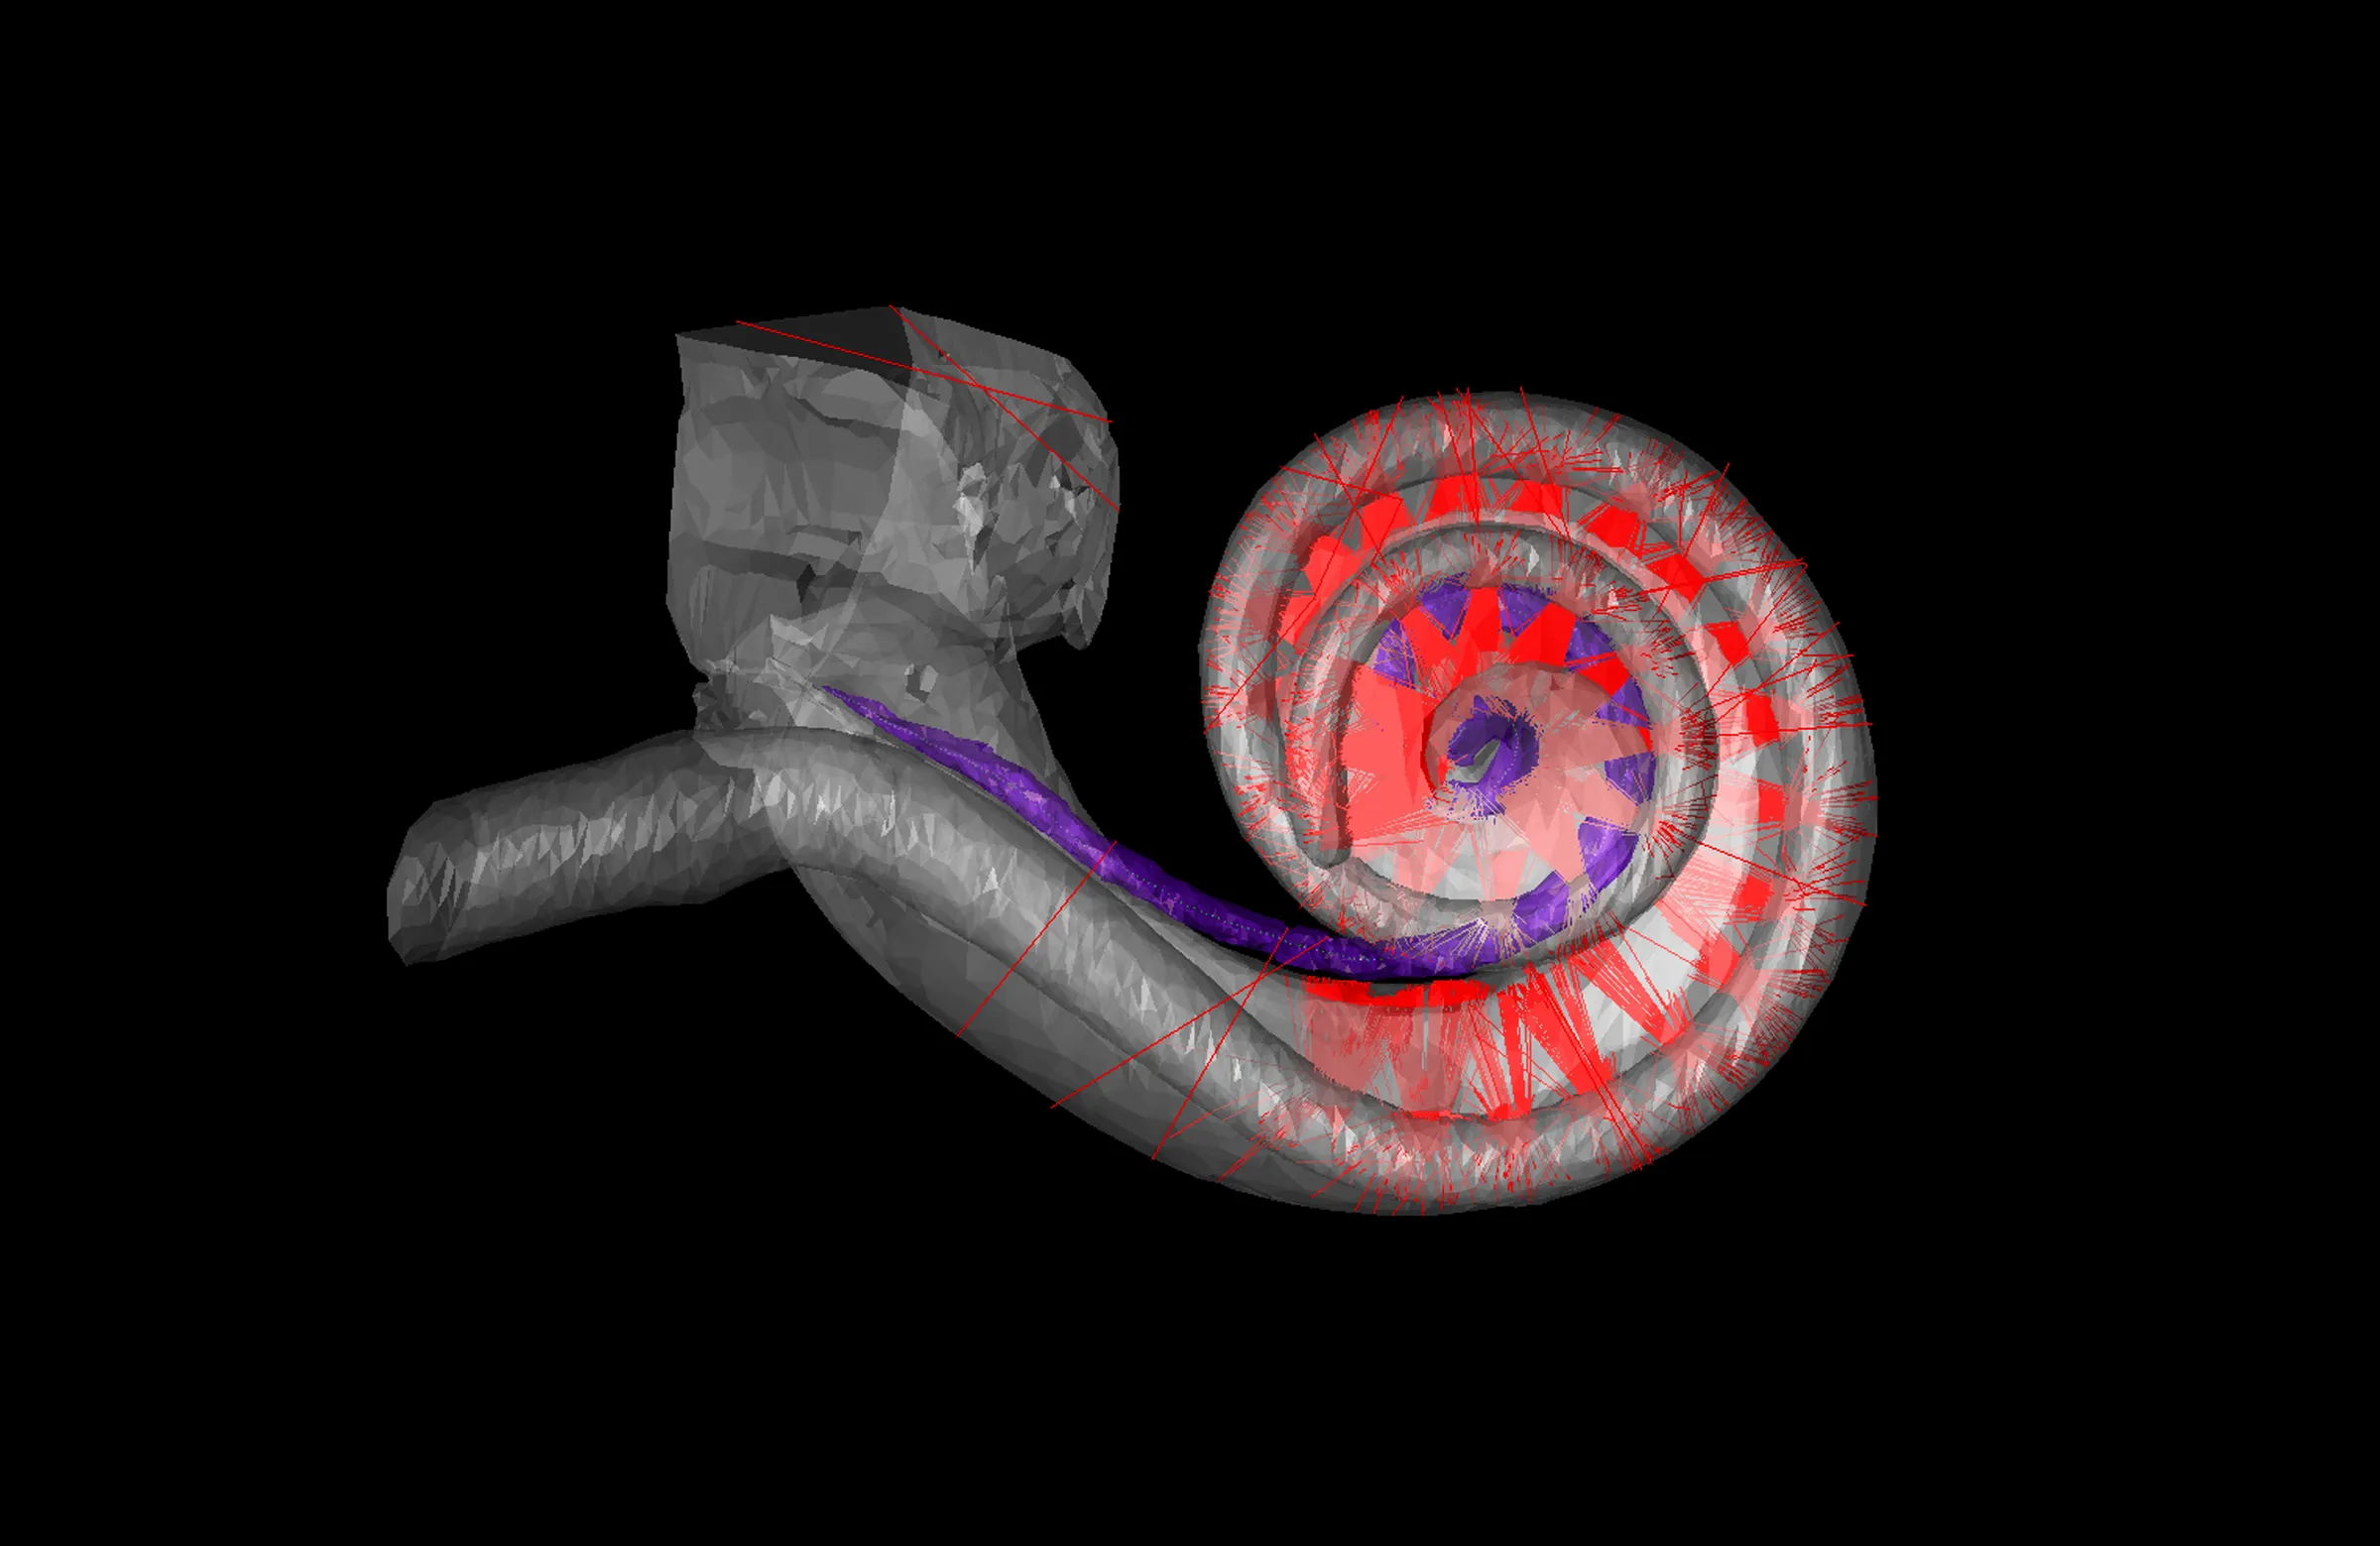

La audición natural es el resultado de vibraciones que golpean estructuras diminutas llamadas células ciliadas dentro de la cóclea en el oído interno. Un implante coclear evita las partes dañadas o disfuncionales del oído y usa electrodos para estimular directamente el nervio coclear, que envía señales al cerebro. Cuando a mis pacientes con problemas de audición les ponen sus implantes cocleares por primera vez, a menudo informan que las voces suenan planas y robóticas y que los ruidos de fondo se difuminan y ahogan las voces. Aunque los usuarios pueden tener muchas sesiones con los técnicos para «sintonizar» y ajustar la configuración de sus implantes para que los sonidos sean más agradables y útiles, hay un límite en lo que se puede lograr con la tecnología actual.

Soy otorrinolaringólogo desde hace más de dos décadas. Mis pacientes me dicen que quieren un sonido más natural, disfrutar más de la música y, sobre todo, una mejor comprensión del habla, especialmente en entornos con ruido de fondo, el llamado problema del cóctel. Durante 15 años, mi equipo de la Universidad de Göttingen, en Alemania, ha estado colaborando con colegas de la Universidad de Freiburg y más allá para reinventar el implante coclear de una manera sorprendentemente contraria a la intuición: usando la luz.